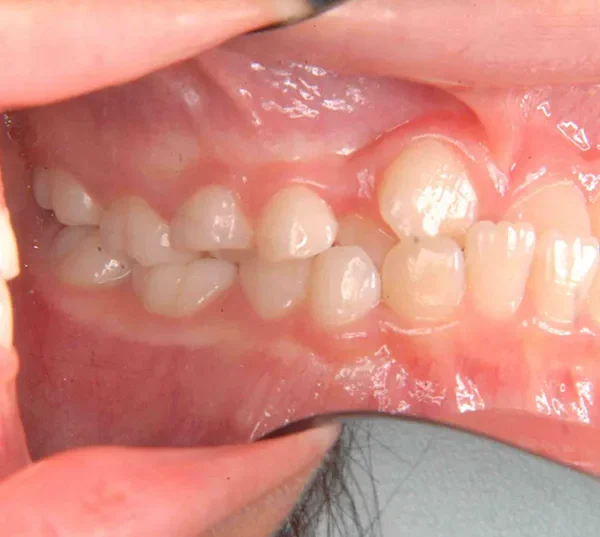

【子供の矯正(一期)】叢生・埋伏歯・受け口・永久歯が生える隙間がない・非抜歯症例・9歳女子【K.T様】

初診時年齢 小学校2年生 (女性) 主訴 受け口・がたがた

診断名 埋伏歯・反対咬合・叢生 装置名

拡大床

特徴 ゆがんで生えている

上の歯と下の歯で舌をはさむ癖がある

状態 永久歯が生える隙間がない(叢生)

受け口(下顎前突/反対咬合)

歯が埋まっている/歯がない(埋伏歯)

受け口で、ガタガタが有りました。

レントゲンを撮ってみると犬歯の萌出方向がずれていました。

先ずは萌出スペースを確保してから開窓術を行い、犬歯を正しい方向へ誘導しました。

マルチブラケット装置は使わずに、最低限の必要な装置を使って目立たないように治療しました。

初診